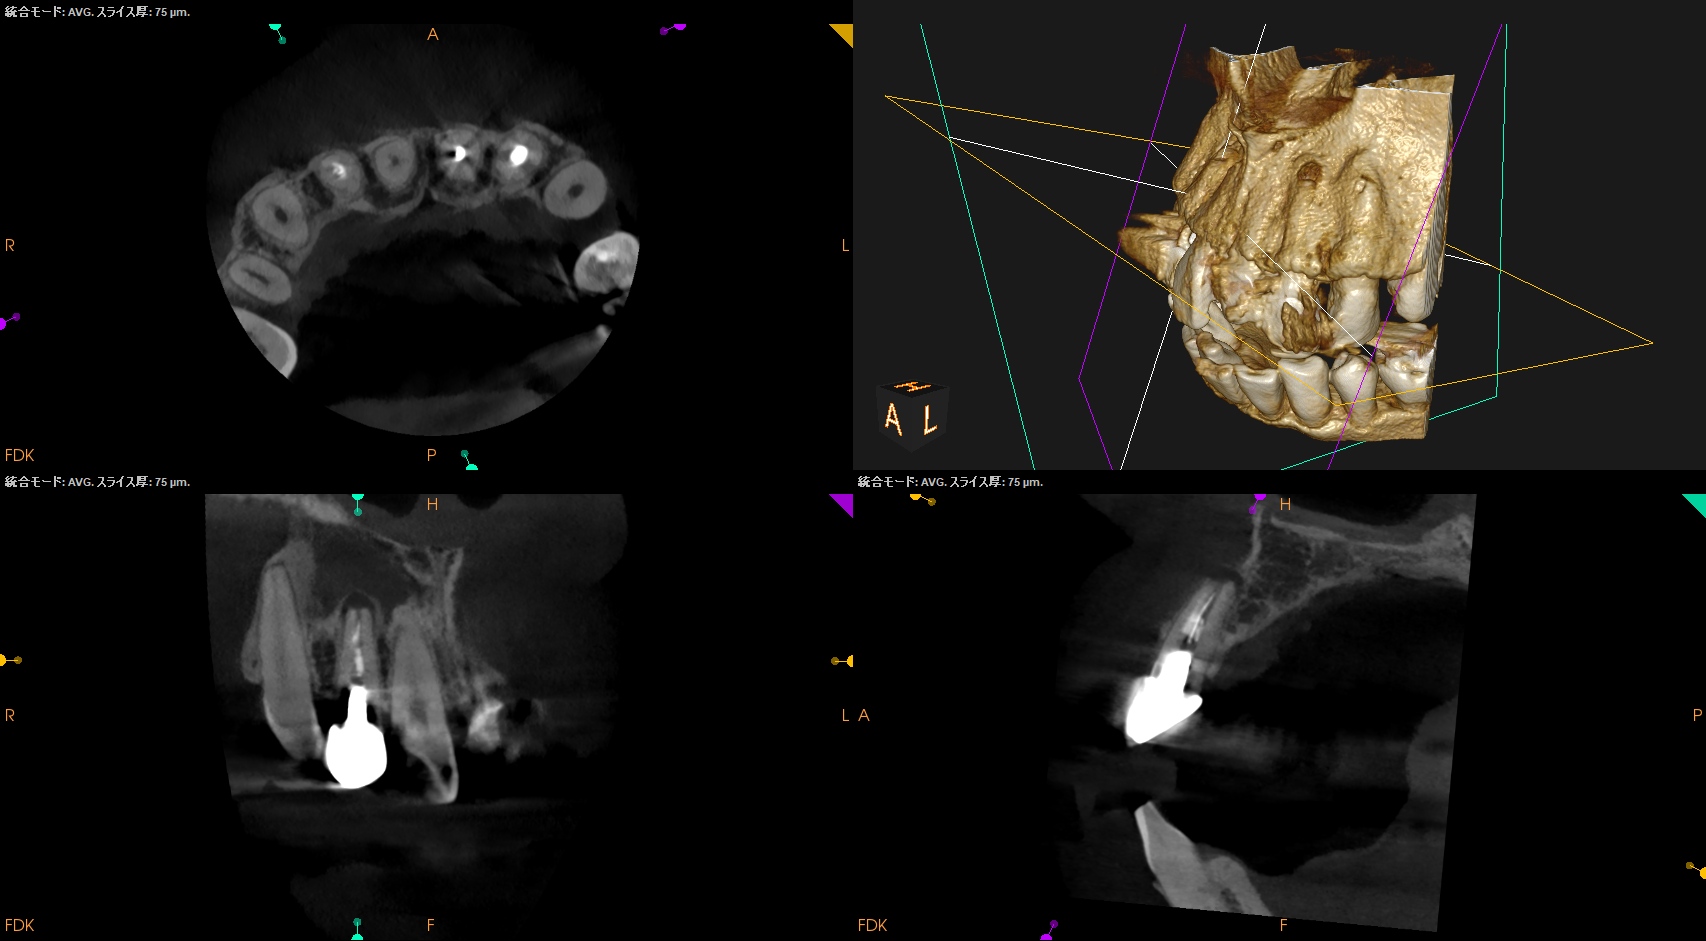

CBCT(2025.1.16)

#7

頬側皮質骨が消失している。

これが圧痛の原因だろう。

#10

#10も#7に同じである。

根管形成・当該部位への根管充填がほぼなされていないように見えることから, 再根管治療へ移行した。